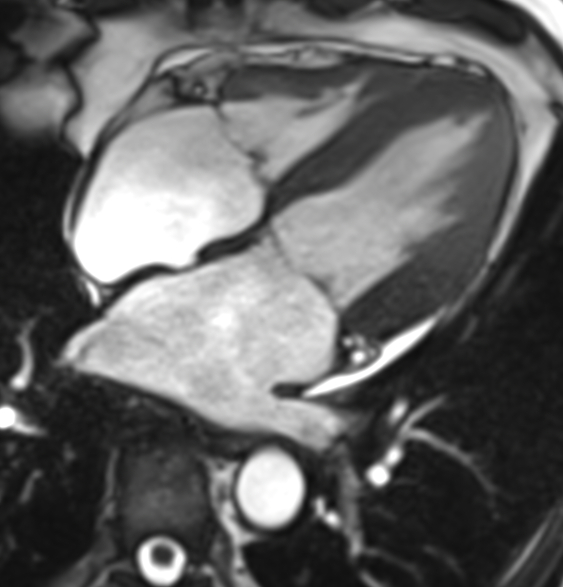

En cardiovasculaire, le CHU de Rouen est reconnu au plan national pour l’exploration du cœur par le scanner et l’IRM. L’unité d’imagerie cardiovasculaire est partie prenante de l’Institut Alain Cribier des Valves Cardiaques et de la plateforme de recherche MiraclAI. Nous disposons de matériels haut de gamme et d’une équipe médicale et para médicale étoffée attirant de nombreux étudiants. Les thématiques de recherche incluent les maladies valvulaires cardiaques et l’étude des cardiomyopathies, notamment la Maladie de Fabry.

• L’IRM: L’IRM cardiaque est largement utilisée dans le domaine des cardiopathies ischémiques (IRM de stress), des aortopathies (Flux 4D) et de tous les types de cardiomyopathies. Un lien étroit est établi entre l’équipe de radiologie clinique et l’unité INSERM EnVI de l’UFR Santé (Pr J Bellien).

IRM 4 cavités